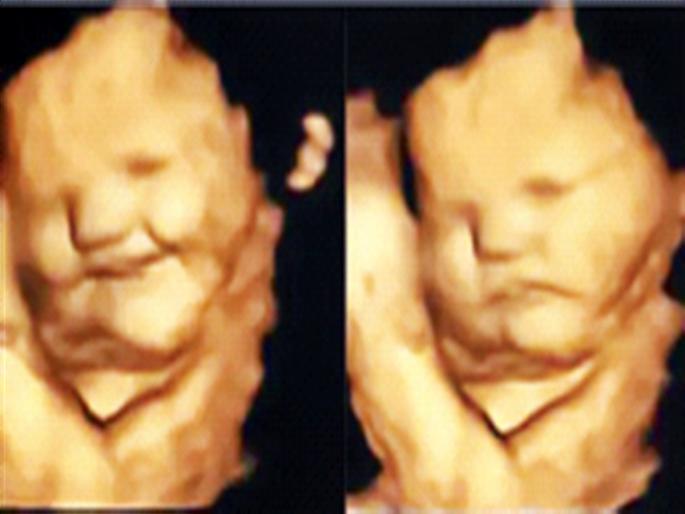

गर्भाशयातील बाळ हसतं आणि नाराजही होतं...

गाजराची कॅप्सूल खाणाऱ्या महिलांच्या गर्भातील मुलांच्या चेहऱ्यावर हसरे भाव दिसले. ज्यांनी कोबीच्या पावडरीची कॅप्सूल खाल्ली त्या महिलांच्या गर्भातील मुलांच्या चेहऱ्यावर रडके भाव दिसून आले. मुलांच्या चेहऱ्यावरील हे सारे हावभाव अत्याधुनिक तंत्रज्ञानाच्या सहाय्याने टिपण्यात आले.

कोबीची कॅप्सूल खाणाऱ्यांपैकी बहुतांश महिलांच्या गर्भातील मुलांना तो स्वाद जाणवल्यानंतर त्यांनी रडका चेहरा केला.गाजराची कॅप्सुल घेतलेल्या महिलांच्या गर्भातील मुलांना ती चव आवडली होती. ज्या महिलांनी काहीही खाल्ले नव्हते त्यांच्या गर्भातील मुलांच्या चेहऱ्यावर कोणतीही खास प्रतिक्रिया उमटलेली नव्हती.